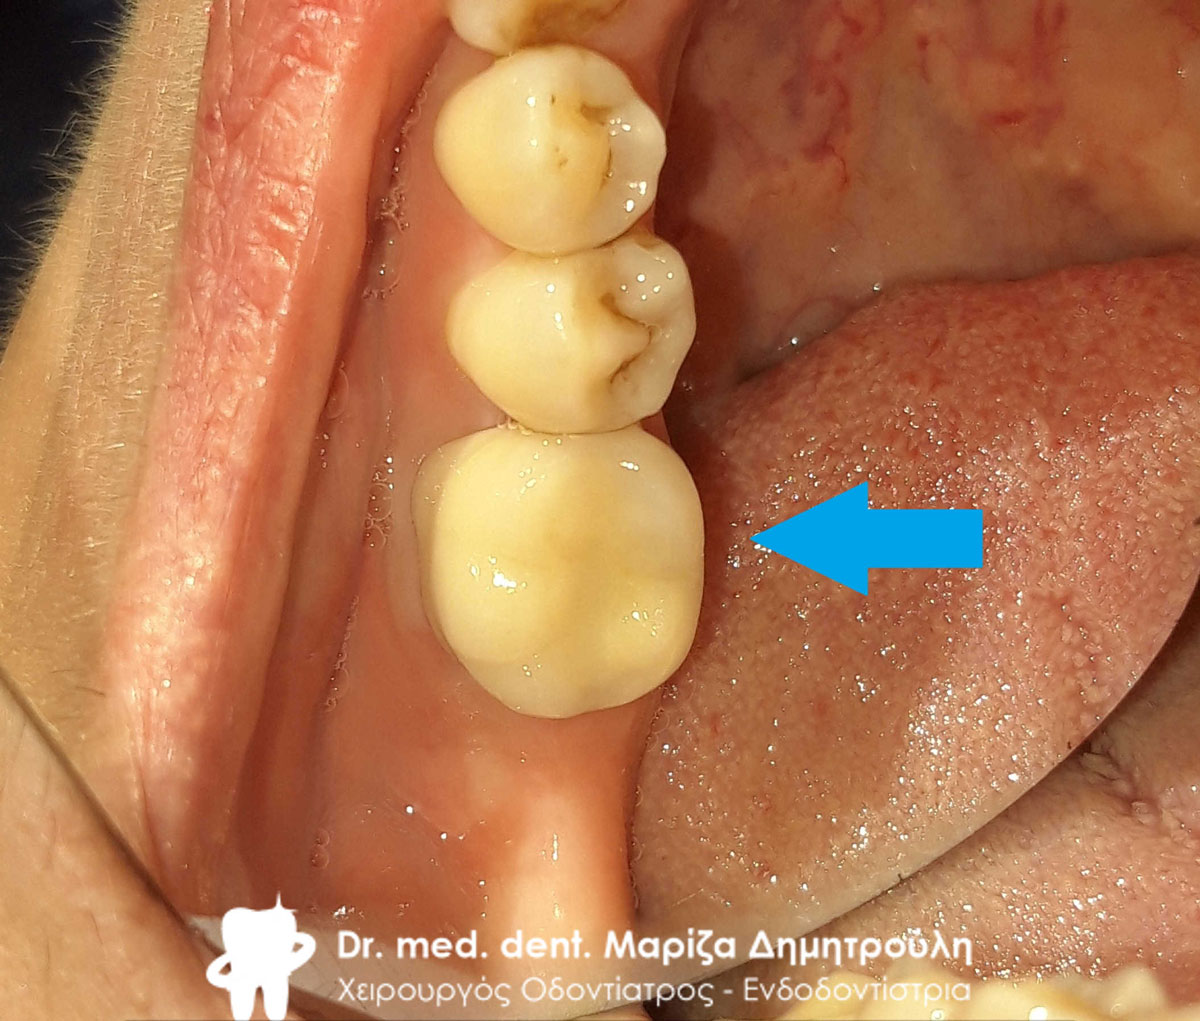

Περιστατικό – Ολοκεραμική θήκη ζιρκονίου στον αριστερο γομφίο της κάτω γνάθου

Ο πρώτος γόμφιος στην αριστερή πλευρά της κάτω γνάθου είχε απονευρωθεί στο παρελθόν. Ο ασθενής δεν θέλησε να καλύψει το δόντι με θήκη, ώστε να είναι πλήρως προστατευμένο με αποτέλεσμα το δόντι να σπάσει (όπως φαίνεται στην αρχική εικόνα). Η λύση θεραπείας ήταν η κατασκευή στεφάνης δοντιού, αφού προηγουμένως το δόντι τροχίστηκε καταλλήλως και ο οδοντοτεχνίτης κατασκεύασε την ολοκεραμική θήκη ζιρκονίου.

Το δόντι είναι πλέον πλήρως προστατευμένο και μπορεί να αντέξει στο πέρασμα των χρόνων.

ΠΡΙΝ

ΜΕΤΑ